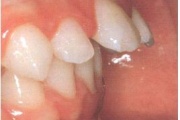

Ravijärgne seis. Jäävhammas on täielikult lõikunud.

Esimese jäävmolaari ektoopiline lõikumine